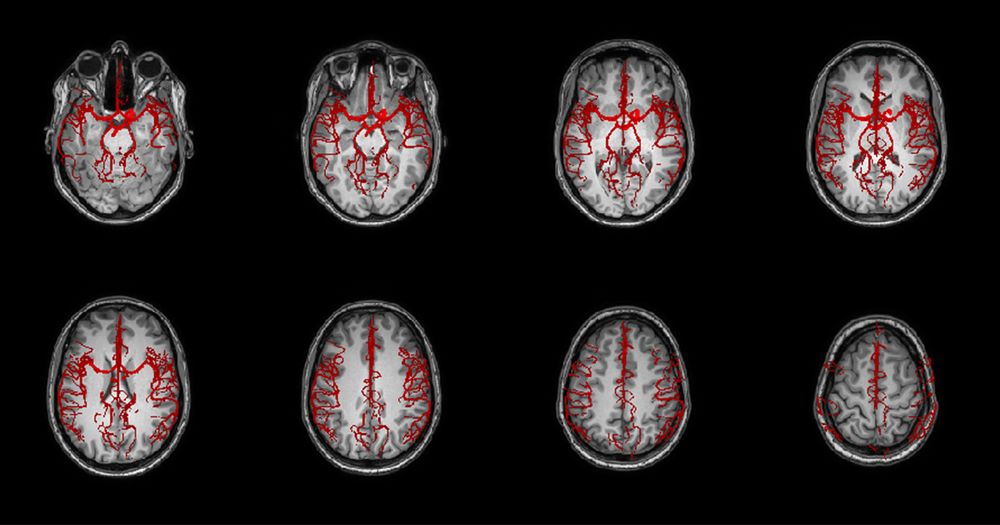

20 novembre 2023Une équipe de recherche établi un lien entre l’historique hormonale des femmes et la détérioration des petits vaisseaux de leur cerveau.

Une équipe de recherche établi un lien entre l’historique hormonale des femmes et la détérioration des petits vaisseaux de leur cerveau.